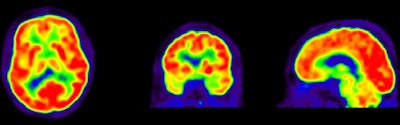

Researchers then proceeded to the PET scans. First, patients were imaged with PiB for 90 minutes to obtain parametric images of the biomarker binding to potential clusters of amyloid. FDG-PET scans were then conducted 45 to 60 minutes after injection and lasted for 15 minutes. Standardized uptake value (SUV) ratios were calculated throughout the brain.

The resulting PET images were visually assessed by a nuclear medicine physician and reported to the neurologists to determine how the additional information changed their initial clinical diagnoses and their confidence in those interpretations.

PiB-PET scans were positive in 40 (61%) of 66 patients with clinical Alzheimer's and in five (28%) of 18 patients with clinical frontotemporal dementia. FDG SUV patterns matched the clinical diagnosis in 58% of patients with Alzheimer's and 33% of patients with clinical frontotemporal dementia, the authors noted.